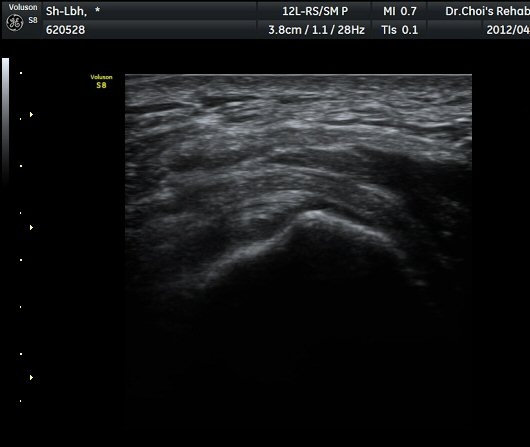

ÃÊÀ½ÆÄ °Ë»ç

´ëÀüÀÚ(gtreater trochanter) ¾ÕºÎºÐ Ⱦ´Ü¸é °Ë»ç¿¡¼­ ´ëÀüÀÚ Ç¥Ãþ¿¡ ¼ÒµÐ±ÙÀÌ °í¿¡ÄÚ ¼¶À¯¾ç ¸ð¾çÀ¸·Î °üÂûµÇ°í ¼ÒµÐ±Ù°ú Àå°æÀÎ´ë »çÀÌ¿¡ ¾à 2mm µÎ²²ÀÇ Á¤¾×³¶ ºÎÁ¾ÀÌ °üÂûµÈ´Ù(±×¸² 1, ³ë¶õ»ö È­»ìÇ¥) . ŽÃËÀÚ¸¦ µÚÂÊÀ¸·Î À̵¿ÇÏ¿© Áߵб٠ÈûÁÙÀÌ °üÂûµÇ°í Áߵб٠ÈûÁÙ ºÎÂøºÎ ÀϺο¡ ¹«¿¡ÄÚ ¿¬°á¼º ¼Ò½ÇÀÌ °üÂûµÇ°í ±× Ç¥Ãþ¿¡µµ Á¡¾×³¶ÀÇ ºÎÁ¾ÀÌ °üÂûµÈ´Ù(±×¸² 2). ȯÀÚÀÇ µÚÂÊ¿¡¼­ ÃÊÀ½ÆÄ À¯µµÇÏ ÁÖ»çÄ¡·á¸¦ À§ÇØ ºñ½ºµëÇÑ È¾´Ü¸é°Ë»ç¿¡¼­ ´ëµÐ±Ù